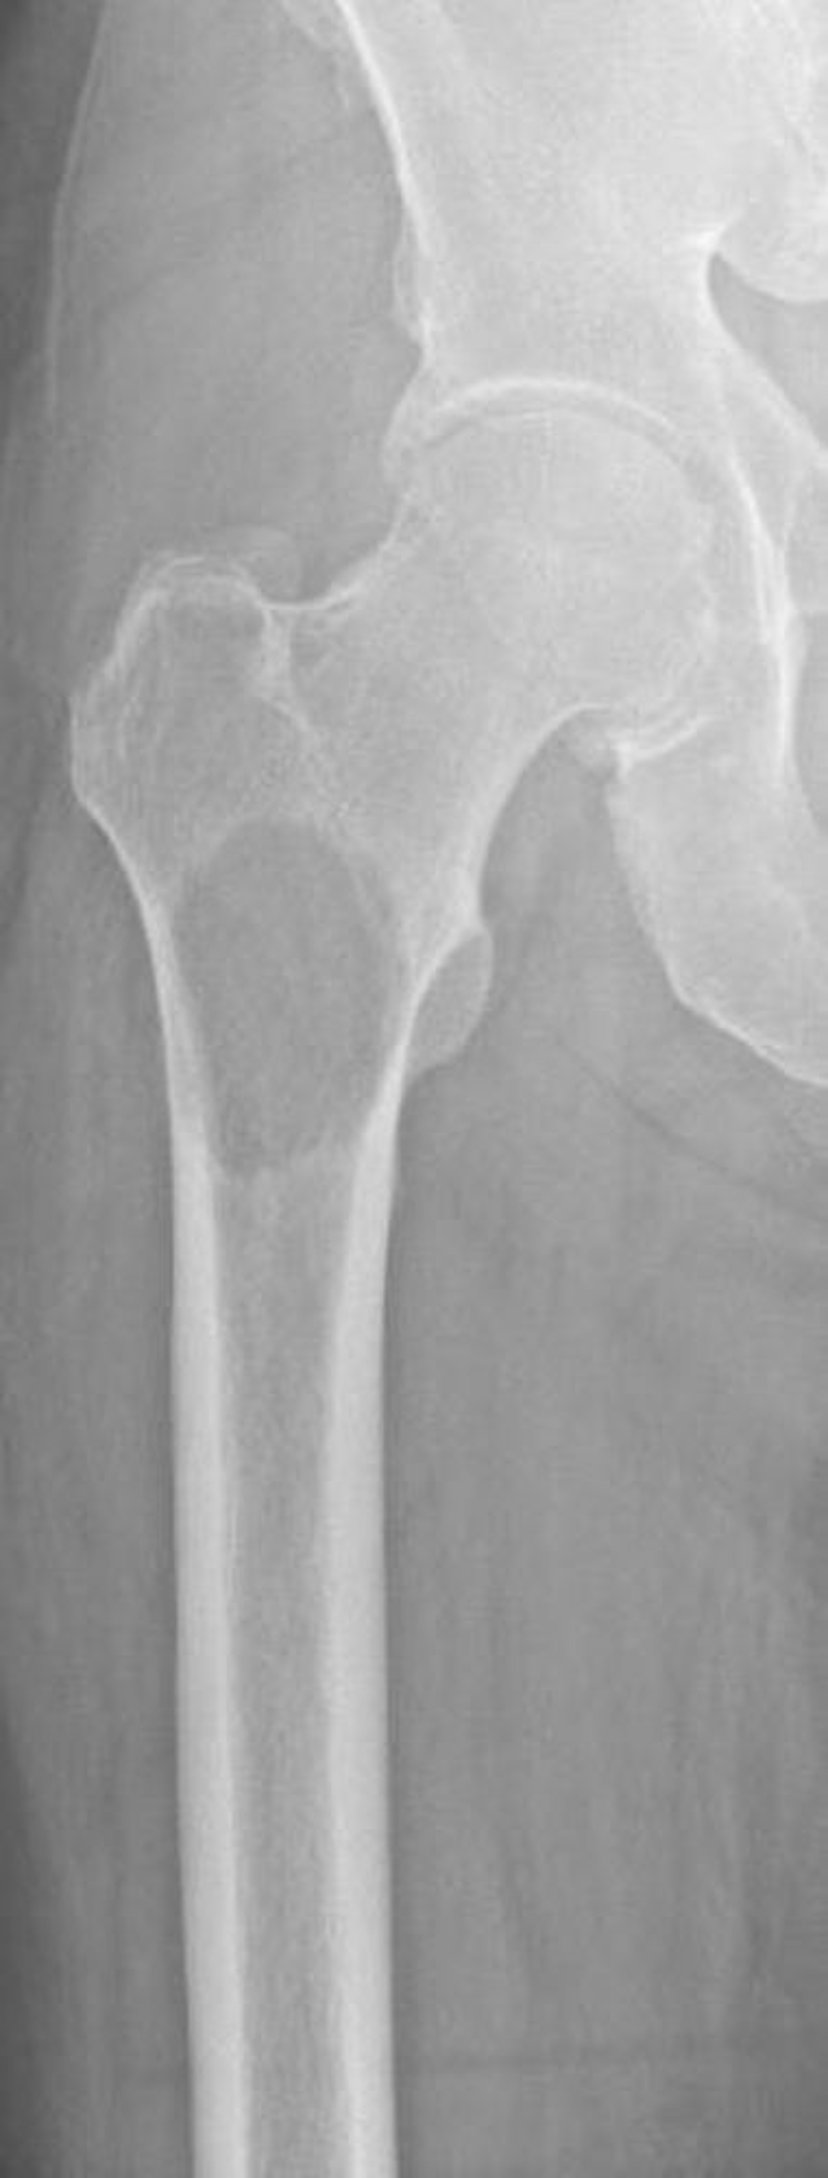

Metástasis líticas en el fémur proximal

Esta imagen muestra destrucción ósea debido a una metástasis secundaria a carcinoma de células renales en el fémur proximal. La ubicación y el grado de destrucción ósea hacen que el riesgo de fractura sea extremadamente alto (fractura inminente).